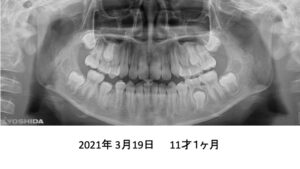

もう1症例、8才4ヶ月の患者さんです。

パノラマでは、永久歯が入るスペースが足りないように見えます。

4年後です。治療は何もしていません。

さらに2年後、全ての歯がちゃんと萌出しました。